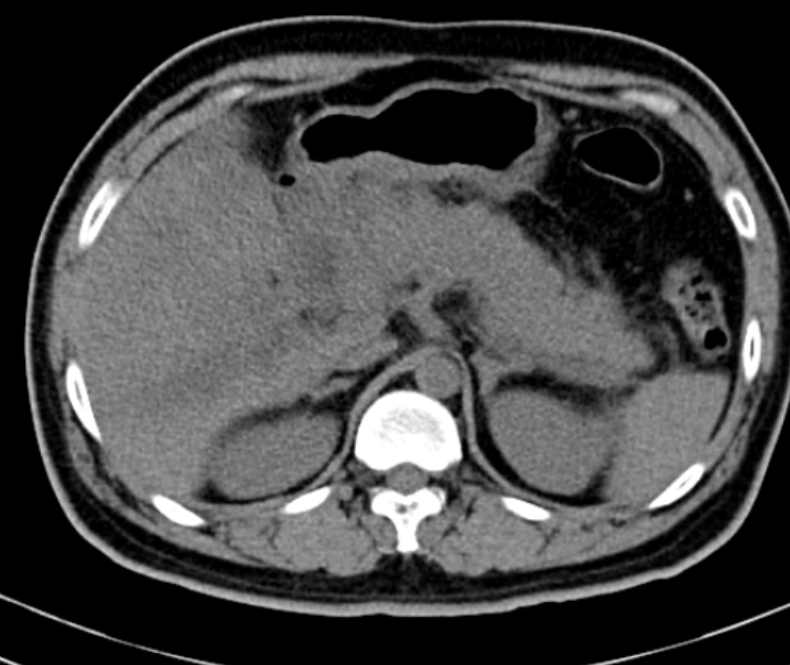

- CT scanner, MRI tụy: Đây là 2 phương pháp có giá trị chính xác trong chẩn đoán cũng như trong tiên lượng bệnh, cho biết rõ hình ảnh, kích thước, mức độ tổn thương ở tụy, quanh tụy, trong ổ bụng.

Hình ảnh CT scanner 1 ca viêm tụy cấp

Siêu âm bụng, CT ổ bụng: Tụy kích thước lớn, phù nề

Hình ảnh CT: Tụy phù nề